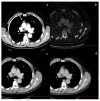

Dual-energy computed tomography (DECT) is one of the most promising technological innovations made in the field of imaging in recent years. Thanks to its ability to provide quantitative and reproducible data, and to improve radiologists' confidence, especially in the less experienced, its applications are increasing in number and variety. In thoracic diseases, DECT is able to provide well-known benefits, although many recent articles have sought to investigate new perspectives. This narrative review aims to provide the reader with an overview of the applications and advantages of DECT in thoracic diseases, focusing on the most recent innovations. The research process was conducted on the databases of Pubmed and Cochrane. The article is organized according to the anatomical district: the review will focus on pleural, lung parenchymal, breast, mediastinal, lymph nodes, vascular and skeletal applications of DECT. In conclusion, considering the new potential applications and the evidence reported in the latest papers, DECT is progressively entering the daily practice of radiologists, and by reading this simple narrative review, every radiologist will know the state of the art of DECT in thoracic diseases.